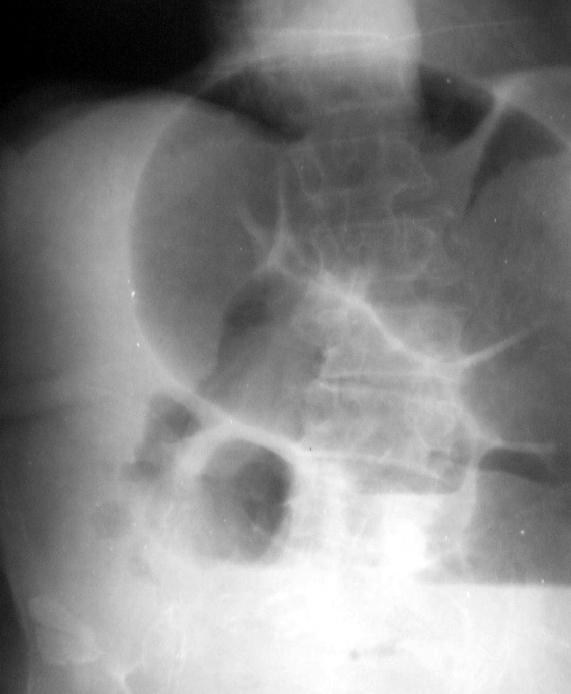

При ректальном исследовании – ампула свободная, стенки ее безболезненные. При обзорной рентгенографии органов брюшной полости выявлены множественные чаши Клойбера и Керкринговы складки в тонкой кишке (см. рисунок). Анализ крови: гемоглобин – 132 г/л, гематокрит – 40%, количество эритроцитов – 3,8•1012/л, лейкоцитов – 13,4•109/л, б – 1%, п – 39%, с – 56%, л –4%. Биохимические анализы в пределах нормы.

Обзорная рентгенограмма органов брюшной полости